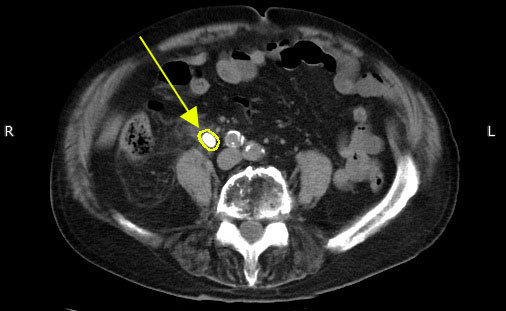

尿路結石のCT

※尿路結石のCT画像